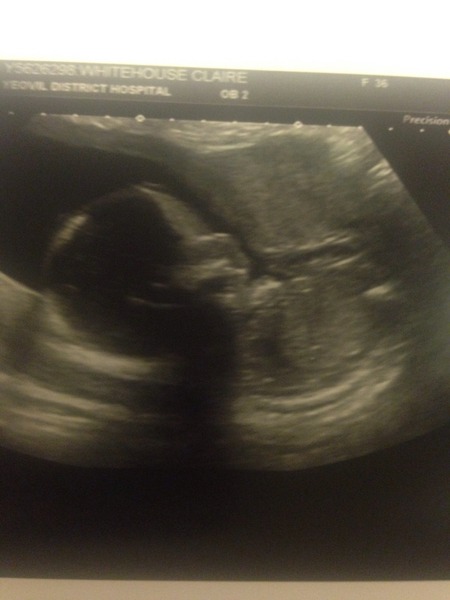

Baby girl all healthy at 20 week scan today - she even gave us a wave!

Brill Mrs mugoo amazing difference between 12&20 weeks x

It's a girl!!!

Huge congratulations to biffleroo and mrsmugoo!! Gorgeous scans and both girls! Congratulations to you both.